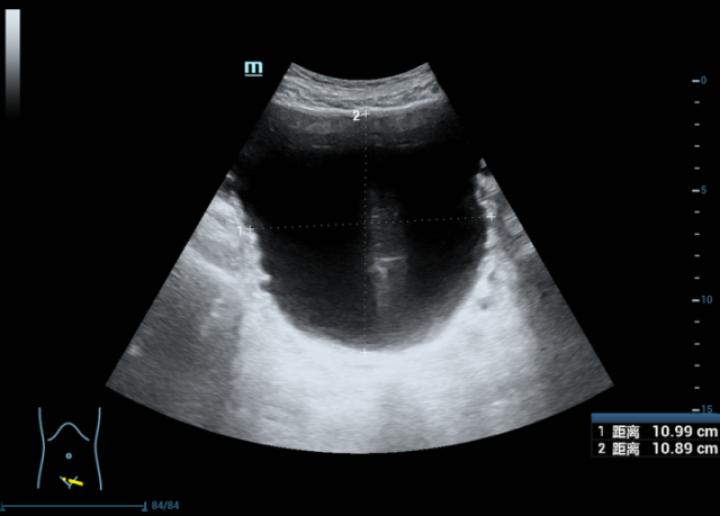

泌尿b超结果求解

输尿管末端扩张